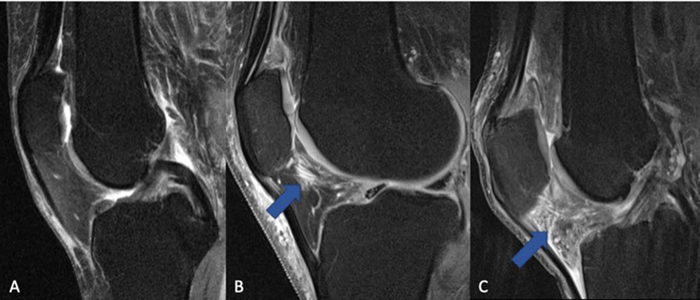

All participants underwent 3T MRI imaging of their knees at the start and end of the study period. This scan generates a magnetic field twice as strong as normal magnetic resonance imaging. Scans were scored for cartilage thickness, composition, and other measurements that served as non-invasive biomarkers of inflammation and arthritis progression.